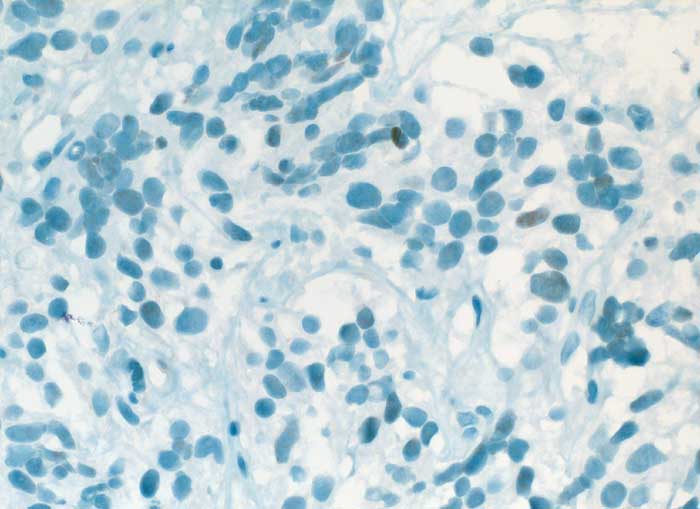

PathoPic ID 6340 - Karzinoid

Karzinoid

benigner Tumor

Lunge

Lunge, Mediastinum mit Thymus

Die spindeligen Tumorzellkerne sind fokal schwach positiv für TTF1

V. a. Tumor pulmonal

Histologie

Immunhistochemie

TTF-1

400